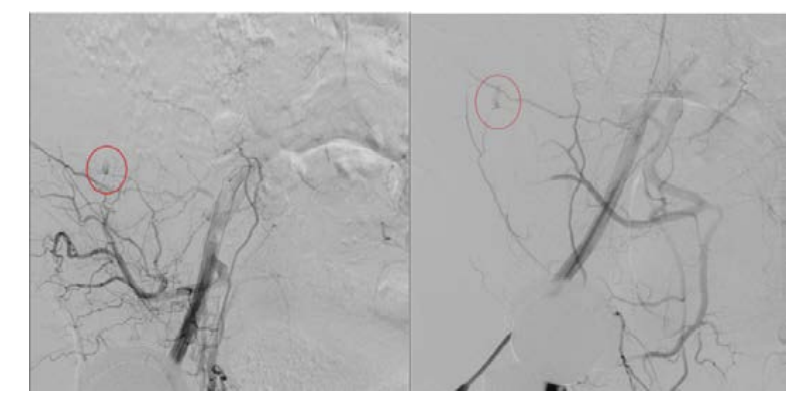

Urgent abdominal CT scan was obtained and revealed a 21 cm right anterolateral abdominal wall intramuscular hematoma that extended to the level of the pelvis with a smaller hematoma in the right groin surrounding the femoral line (Figure 2). The patient was taken back to the catheterization lab and using the retained right common femoral sheath in place, repeat angiography with digital subtraction revealed perforation of a distal branch of the right superficial iliac artery (Figure 3).